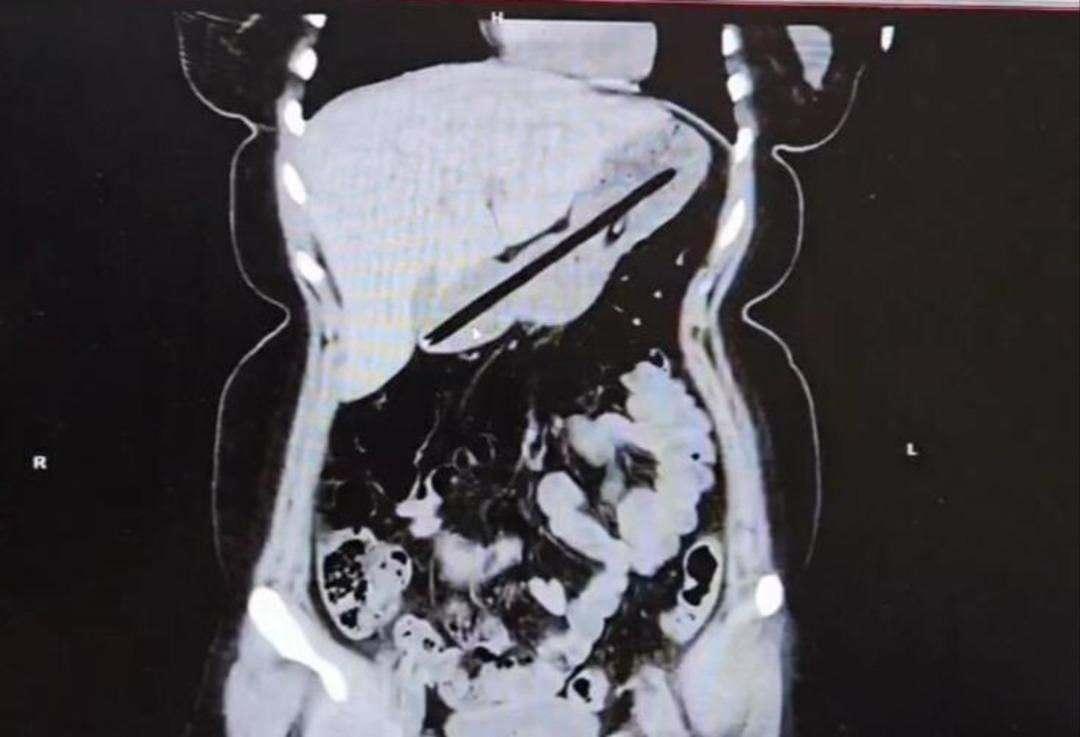

Operasyonu gerçekleştiren Dr. Öğretim Üyesi Adem Aslan, ilk kez böyle bir vakayla karşılaştıklarını belirterek, “22 yaşındaki bayan hastamız kalem yutma şikayetiyle ilçe devlet hastanemize başvurmuştu. Tomografisinde midesinde yabancı cisim olduğu görüldü. Biz de tetkiklerimizde midesinde kalem olduğunu gözlemledik. Daha önce toplu iğne, kemik parçası gibi yabancı cisimlerle karşılaşıyorduk ama bu kadar uzun ve ince bir cisim ilk kez karşımıza çıktı. Midenin boşalması için bir gün bekledik ve ertesi gün yaptığımız endoskopide hastanın bir değil iki kalem yuttuğunu gördük.” ifadelerinde bulundu.